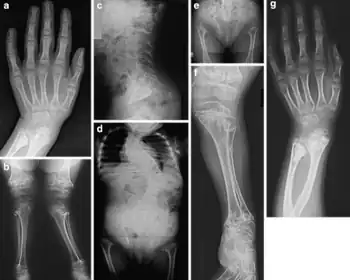

Variant of SMD type A4-a)Metaphyseal involvement of the distal radius and ulna b)metaphyseal involvement and severe coxa valga c) lumbar lordosis d) spinal scoliosis in spite of 6 years of bracing e) delayed ossification of pubic bones f) severe metaphyseal changes and genu valgum deformity g)severe metaphyseal involvement of forearm bones